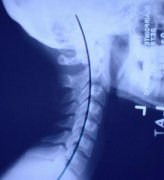

河南强脊炎专科医院:强直性脊柱炎患者早期会表现颈

强直性脊柱炎的早期症状有哪些?郑州治疗强直医院介绍许许多多的强直性脊柱炎疾病的患者,…[详情]